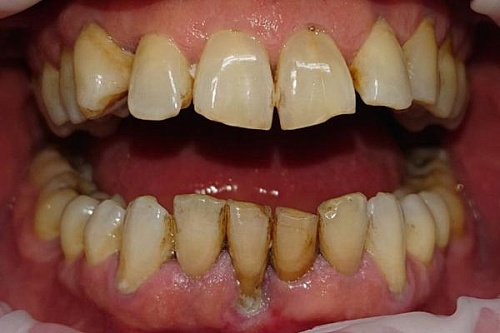

Профессиональная гигиена ультразвуком и Air Flow

Лечение зубов с использованием профессиональной гигиены, ультразвука и технологии Air Flow, мужчина 32 лет.

Профессиональная гигиена ультразвуком и Air Flow До

Профессиональная гигиена ультразвуком и Air Flow После